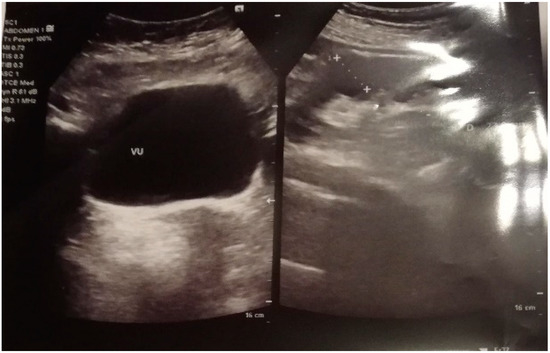

- Gastroenterology exam: normal function, lack of gastrointestinal bleeding, and no hepatic AVM identified.